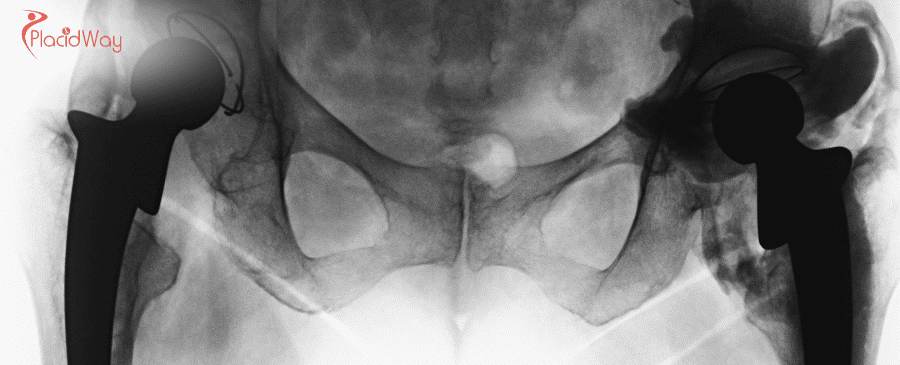

Understanding Total Hip Replacement Surgery

A total hip replacement, or total hip arthroplasty, is a surgical procedure in which the damaged parts of the hip joint are removed and replaced with artificial components, known as a prosthesis. The goal of the surgery is to relieve pain, improve mobility, and restore function to the hip joint.

This procedure is most commonly performed to address severe arthritis, such as osteoarthritis or rheumatoid arthritis, that has not responded to conservative treatments. It can also be necessary following a hip fracture or other conditions that lead to the breakdown of the hip joint.

Your journey begins with a remote consultation. You will share your medical records, X-rays, and diagnostic reports with the Turkish medical team. The orthopedic surgeon will review your case, confirm your candidacy for the surgery, and recommend a specific type of implant and surgical approach.